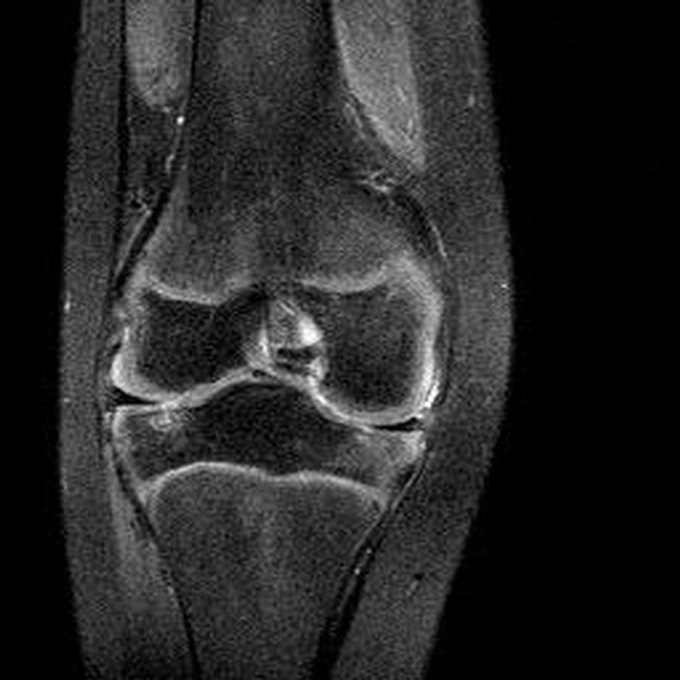

Haemophiliearthropathie bei Haemophilie A.

Arthropathia ARC123 Haemophiliearthropathie bei Haemophilie A.

MRT (high)